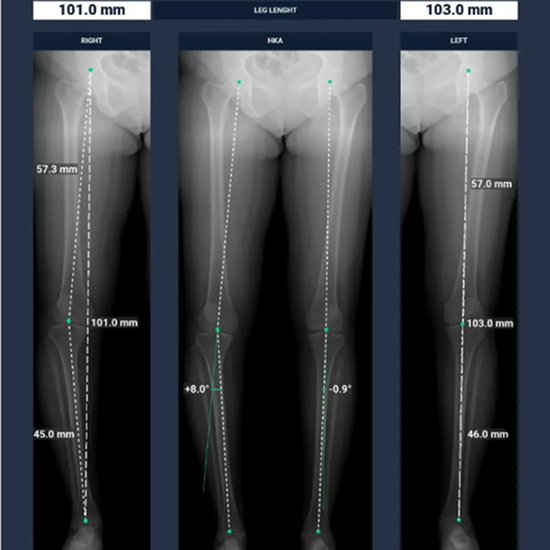

BoneMetrics automatically performs standard measurements for the feet, legs, pelvis/hips, and spine.

Through accurate point placement and easily understandable displays, the introduction of the software allows you to direct your attention to more critical tasks.

By introducing AI-supported standardization, variability can be reduced and reproducibility can be ensured.

Clinical studies prove that BoneMetrics matches the expertise of MSK radiologists, enabling your practice to provide the best possible service to patients.

BoneMetrics instinctive reports seamlessly integrate with your X-ray and EOS acquisitions, streamlining the interpretation procedure and elevating the satisfaction of your prescribers.